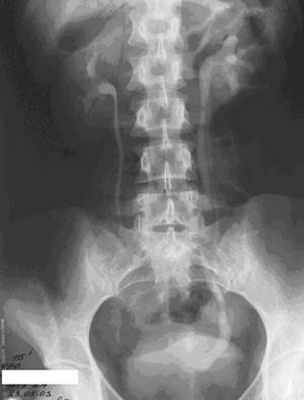

Обзорная урограмма,

выполняемая в условиях естественной контрастности, охватывает область от верхнего

края почек до начала мочеиспускательного канала. В случае умеренно выраженной

внутрибрюшной и забрюшинной жировой клетчатки на обзорных урограммах визуализируются контуры почек, по

которым можно оценить их форму, размеры и расположение. Обзорная урография

позволяет обнаружить рентгеноконтрастные конкременты в почке или мочеточнике.

Но в большинстве случаев данных обзорной урографии

недостаточно. В основном обзорный снимок лишь указывает на наличие

«лишних» теней, свидетельствующих о той или иной патологии. С помощью

обзорной урографии невозможно оценить состояние тканей внутри почки или оценить

степень нарушения оттока мочи. Обнаружив на обзорном снимке камень в проекции

почки или мочеточника, врач не может определить его точное расположение.